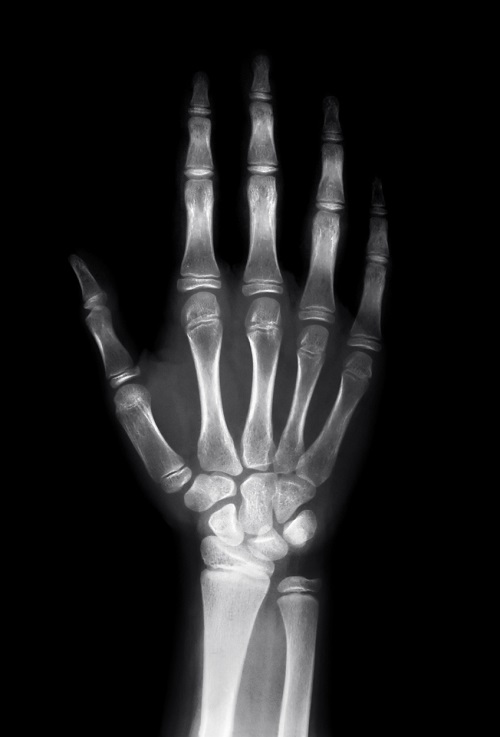

[DataNET] 스마트폰 사용이 초래한 '손목터널증후군', 과도한 사용 줄여야